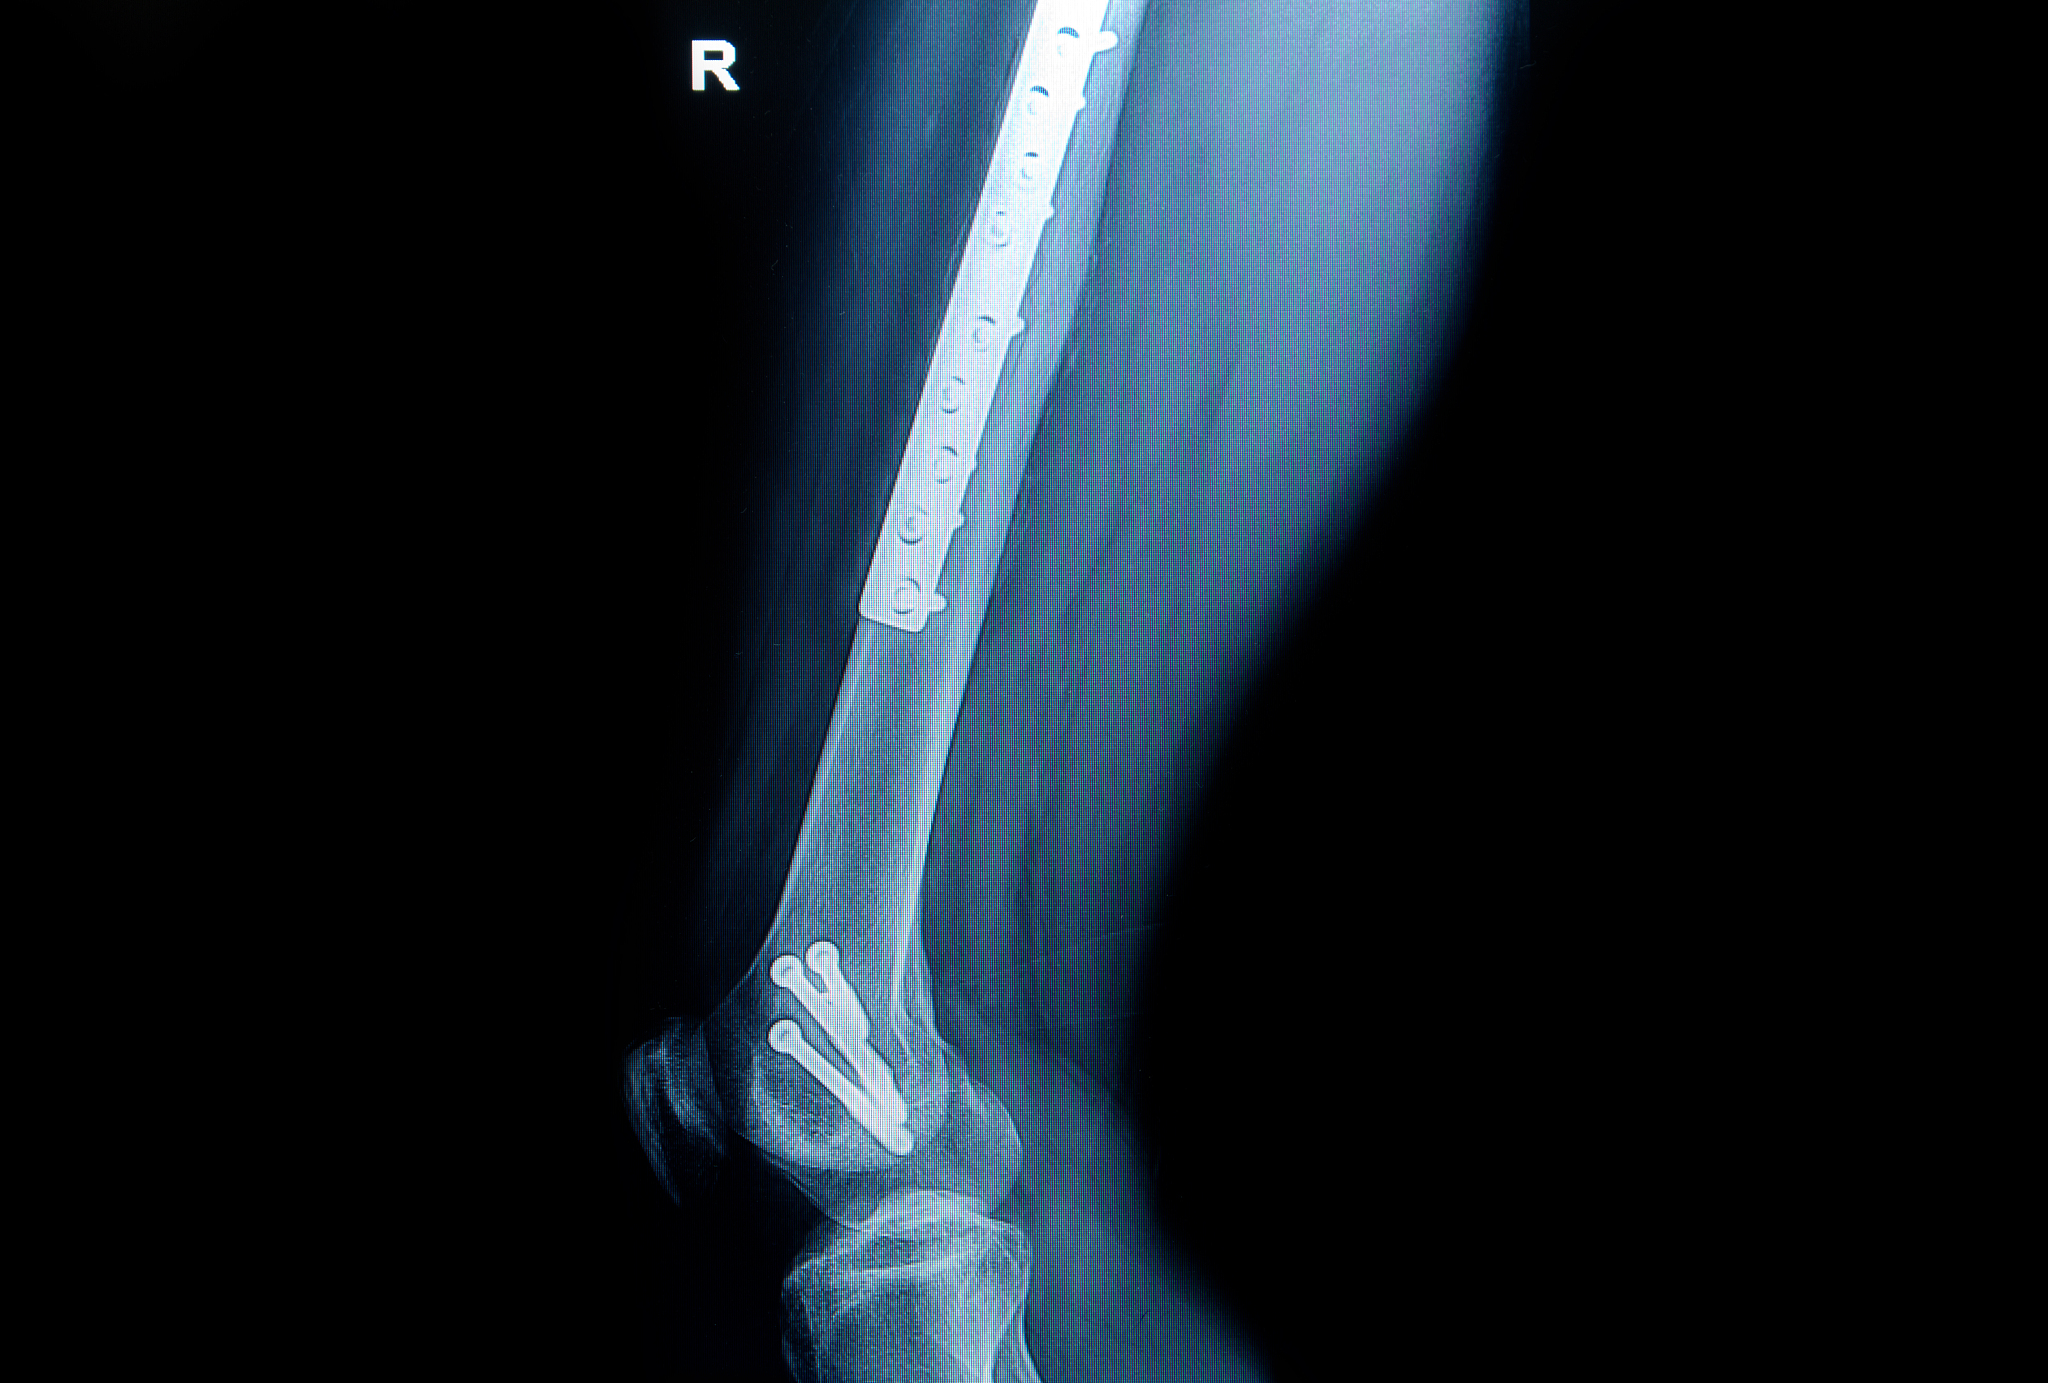

其次,在术前准备上,整体护理模式注重患者的教育和指导,帮助患者和家属了解手术的过程、风险和预后,提高患者的手术合作性和自我管理能力。对于老年股骨粗隆间骨折手术来说,术前准备包括准备手术所需的检查、化验、影像学检查等,同时也包括术前的营养支持、体力训练和心理支持等方面。整体护理模式强调术前准备的个性化,根据患者的具体情况制定个性化的护理计划,以提高手术的成功率和患者的术后康复效果。

再次,在术中管理上,整体护理模式强调团队合作和多学科协作,提高手术的安全性和效果。对于老年股骨粗隆间骨折手术来说,术中管理包括麻醉管理、手术操作和术中监测等方面。整体护理模式强调术中的综合护理,包括围手术期的体温管理、出血控制、感染预防等,以减少手术并发症的发生。